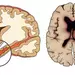

호주ㆍ중국 공동 연구팀, 2만2,800명 11년간 추적 조사 젊은 나이에 고혈압 진단을 받으면 뇌 용적이 줄면서 치매에 걸릴 ..